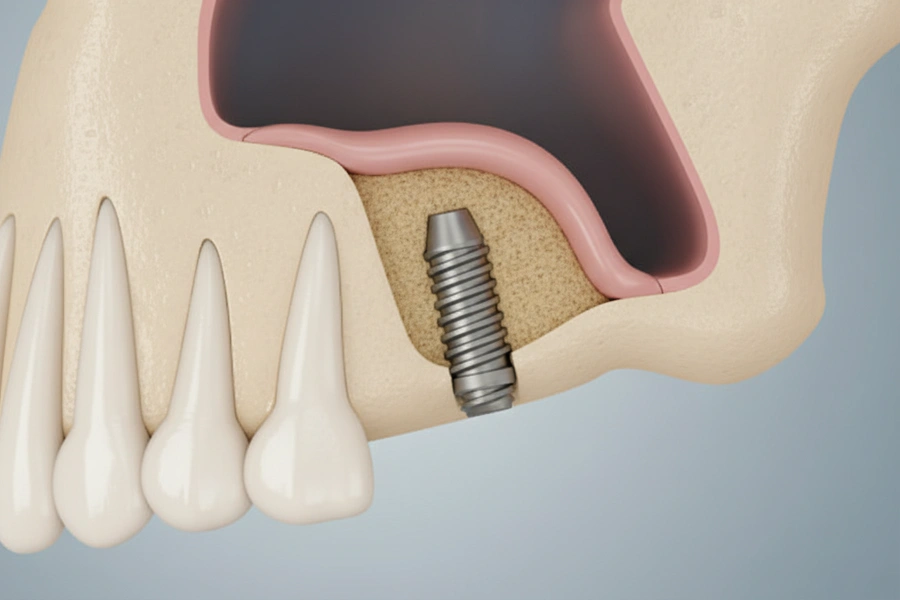

インプラントとは

「人工の歯の根」インプラントとは、チタン製の人工物です。失われた歯の根の代わりに、長さ約10mmのインプラント体をあごの骨に埋め込みます。これにより、まるで自分の歯のようにしっかりと噛める土台を作ります。

骨と一体化する

「チタン」の特性インプラントの素材であるチタンには、骨と一体化して強固に結合する性質があります。これを「オッセオインテグレーション」と呼び、インプラントが長期的に安定する秘訣です。インプラント体の表面には、骨との結合をより確実にするための特殊な加工が施されており、メーカーごとの性能を左右する重要なポイントとなっています。当院では、信頼性の高いメーカーのインプラントを厳選しています。

03インプラント手術

局部麻酔をして、あごの骨にインプラントを埋め込む手術を行います。多くの患者様が大きな痛みを訴えることはありません。当院は患者様の身体への負担を最小限に抑えるよう配慮し、些細な変化にも気づけるよう、細心の注意を払って手術を進めます。ご予算に応じて、安心と実績のあるインプラント材をご提案いたします。

05人工歯の土台の設置

インプラントと骨が安定したら、インプラントと人工歯をつなぐ土台(アバットメント)を装着します。当院では、感染リスクや調整のしやすさを考慮し、インプラントと土台が別々になっているタイプを使用します。これにより、より安全で精密な治療を行うことができます。